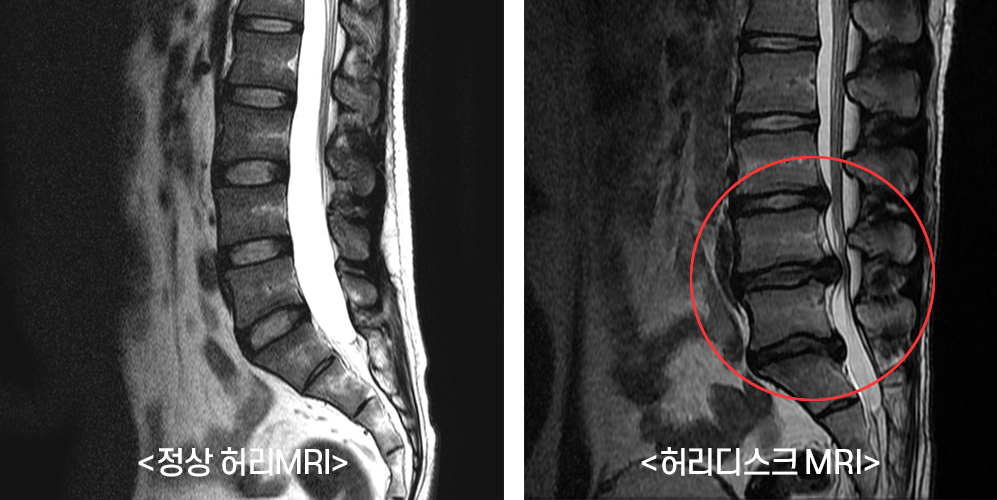

허리디스크 증상 알아보자!

허리디스크는 현대인에게 매우 흔한 건강 문제 중 하나로, 많은 사람들이 이 증상으로 고생하고 있습니다. 허리 건강은 우리의 일상생활에 큰 영향을 미치기 때문에, 이를 잘 관리하기 위해서는 증상을 조기에 이해하고, 정기적인 체크가 필요합니다.이번 포스트에서는 허리디스크의 증상과 함께 허리 건강 체크리스트를 제공하여, 여러분의 건강을 지키는 데 도움이 되고자 합니다.👉허리디스크에 좋은 운동 더 확인해보자!허리디스크란 무엇인가요?허리디스크는 척추 뼈 사이에 위치한 연골과 같은 구조물인 디스크가 손상되어 발생하는 상태입니다. 보통 나이가 들어감에 따라 이러한 문제가 발생하는 경향이 있지만, 무리한 운동이나 잘못된 자세로 인해 젊은 사람들도 겪을 수 있습니다. 허리디스크는 척추 신경을 압박하여 여러 가지 증상을..